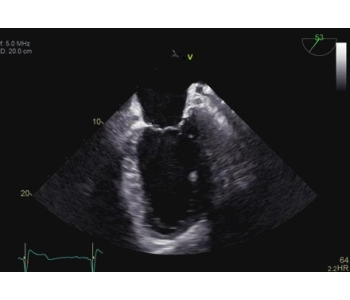

The 4D ICE NUVISION Catheter offers real-time volumetric imaging, a 90x90 field of view, 4D color Doppler flow capabilities, and an independently rotating tip, making it an ideal choice for left atrial appendage closure (LAAC) procedures.